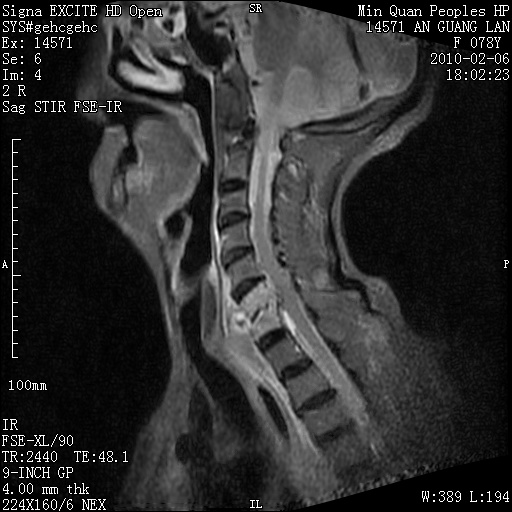

标题: MRI2763:C6、C7椎体病变性质?

f,78y,颈部与双上肢阵发性剧痛40余天。ct可见c6、c7椎体虫蚀样破坏,其间椎间隙变窄(没有图片资料可供上传)。